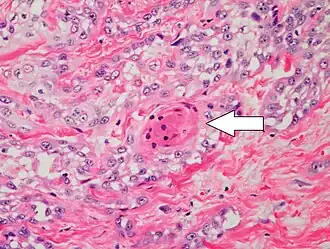

-

Well-differentiated (yet invasive) cSCC, showing prominent keratinization. It may form pearl-like structures where dermal nests of keratinocytes attempt to mature in a layered fashion. Well-differentiated cSCC has slightly enlarged hyperchromatic nuclei with abundant amounts of cytoplasm. Intercellular bridges will frequently be visible.[12] -

Poorly differentiated, where attempts at keratinization are often no longer evident. This is a clear-cell squamous-cell carcinoma. The dysplastic cells infiltrated cords through the dermis. Poorly differentiated cSCC has greatly enlarged pleomorphic nuclei showing a high degree of atypia and frequent mitoses.[12] -

Poorly differentiated clear-cell squamous-cell carcinoma. For this type of cSCC, immunostains will likely be required to classify it unless other areas of the tumor show obvious squamous-cell features, such as seen here (arrow).